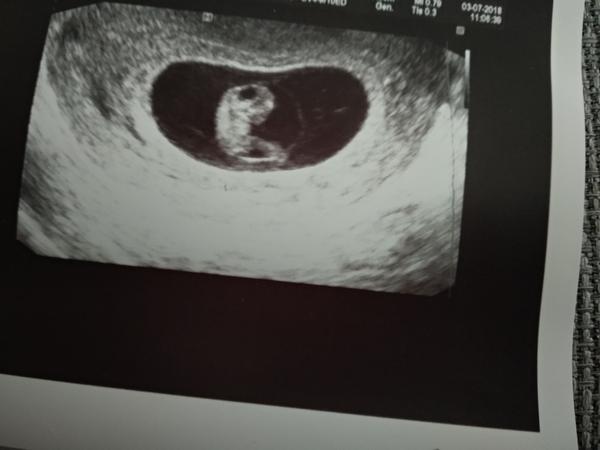

Včera jsme byli na kontrole jsme 7+4 a vše v pořádku ..srdíčko blikalo... tatinek poprvé viděl malinké❤...objednala nás na krev 16.7 s tým že udelá prukazku, a pro zvracení musím být doma odpočivat ,predepsala mi i nejaké čipky..tak uvidíme